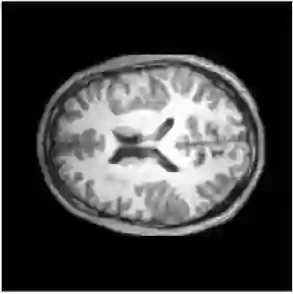

Reconstructing under-sampled k-space measurements in Compressed Sensing MRI (CS-MRI) is classically solved with regularized least-squares. Recently, deep learning has been used to amortize this optimization by training reconstruction networks on a dataset of under-sampled measurements. Here, a crucial design choice is the regularization function(s) and corresponding weight(s). In this paper, we explore a novel strategy of using a hypernetwork to generate the parameters of a separate reconstruction network as a function of the regularization weight(s), resulting in a regularization-agnostic reconstruction model. At test time, for a given under-sampled image, our model can rapidly compute reconstructions with different amounts of regularization. We analyze the variability of these reconstructions, especially in situations when the overall quality is similar. Finally, we propose and empirically demonstrate an efficient and data-driven way of maximizing reconstruction performance given limited hypernetwork capacity. Our code is publicly available at https://github.com/alanqrwang/RegAgnosticCSMRI.